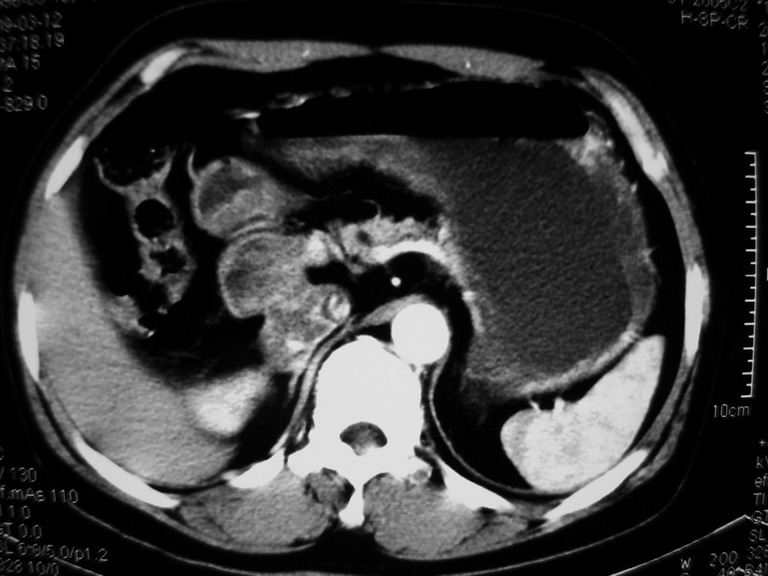

接着往下一贴看,有静脉期和延迟期,在看看和下腔静脉及十二指肠的关系,腔静脉内是不是栓子?

考虑肝右叶与尾叶交界区肝癌(部分外生),侵犯下腔静脉并下腔静脉瘤栓形成。